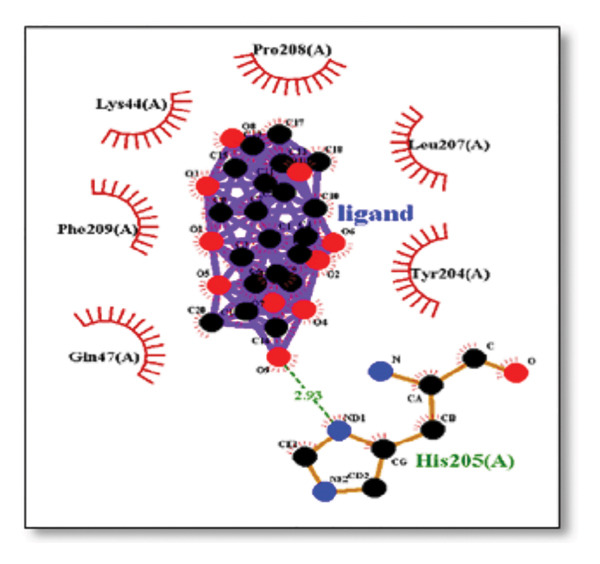

3.3. AutoDock Vina Results: Clusterin Receptor

Ginkgolide showed the strongest binding at −13.98 kcal/mol, interacting with HIS205. Other potent ligands were ginsenosides (−8.02 kcal/mol), which formed contacts with PHE240, and berberine (−6.46 kcal/mol), interacting with ASN291. Resveratrol also exhibited favorable binding (−6.34 kcal/mol), forming H‐bonds with PRO212 and ALA373. Cannabidiol had the weakest binding at −3.56 kcal/mol, interacting with ARG292:HE1. The weakest binder was cyanidin (−3.92 kcal/mol), which showed no hydrogen bond interactions.

For reference drugs, donepezil (−5.65 kcal/mol) with GLY378, Figure 3 illustrates the binding characteristics of natural ligands and reference drugs for the clusterin receptor.

The in silico predictions for ginkgolide’s interactions with sortilin, clusterin, and tau are well‐supported by the established structural and functional mechanisms of these proteins in scientific literature. For sortilin, the predicted interaction with ARG292 and TYR318 is consistent with the protein’s known structure. Studies have shown that its large, ten‐bladed β‐propeller domain is the primary ligand‐binding site; ARG292, often positioned near the VPS10P domain, likely provides critical electrostatic stabilization, while TYR318 contributes $\pi‐\pi$ or $\pi$‐cation interactions, collectively stabilizing the ligand–receptor complex. This binding site overlaps with regions known to undergo conformational change during ligand recognition, suggesting ginkgolide may allosterically modulate the receptor’s trafficking function. A 2017 study by [ref. 38], for example, demonstrated how conformational changes in this domain, caused by pH, disrupt binding sites. Similarly, a review by Quistgaard et al. [ref. 39] highlights how the architecture of the VPS10 domain, which includes these residues, is vital for its function. For clusterin, the predicted interaction with HIS205 is supported by the protein’s established role as a molecular chaperone that prevents protein aggregation.

Histidine residues are frequently involved in coordinating chaperone‐substrate interactions. The binding of ginkgolide at HIS205 suggests it may stabilize the active conformation of the chaperone, thereby enhancing its ability to bind to and inhibit the formation of amyloid fibrils, a key mechanism reinforced by recent research published [ref. 40]. This research has consistently reinforced that clusterin’s ability to bind to and inhibit the formation of amyloid fibrils is a key mechanism of action, particularly in neurodegenerative diseases. While direct mention of HIS205 is rare, its chaperone function is broadly understood to rely on such key residues. Elias et al. [ref. 41] and Carini et al. [ref. 42] confirm that clusterin’s role in inhibiting aggregation is a major focus of current research. Finally, the predicted binding to HIS329 in tau is highly significant and directly corroborated by recent literature. HIS329 is explicitly located within the microtubule‐binding repeat domain, which is the primary site for tau’s pathological self‐aggregation. Ginkgolide’s predicted binding at this position is a direct mechanism of aggregation inhibition, suggesting it acts as a steric wedge or “capping agent” to prevent the formation of toxic beta sheet structures, aligning with similar strategies explored. Studies have explicitly identified histidine residues within the microtubule‐binding repeat domain as participants in tau’s self‐aggregation process. Hernández et al. [ref. 43] specifically names residues like H329 as being involved in this mechanism. Molecular docking and simulation studies, such as one from 2025 by Saha and Natarajan [ref. 44], also focus on targeting this domain with small molecules to inhibit tau pathology, providing strong support for the in silico predictions.